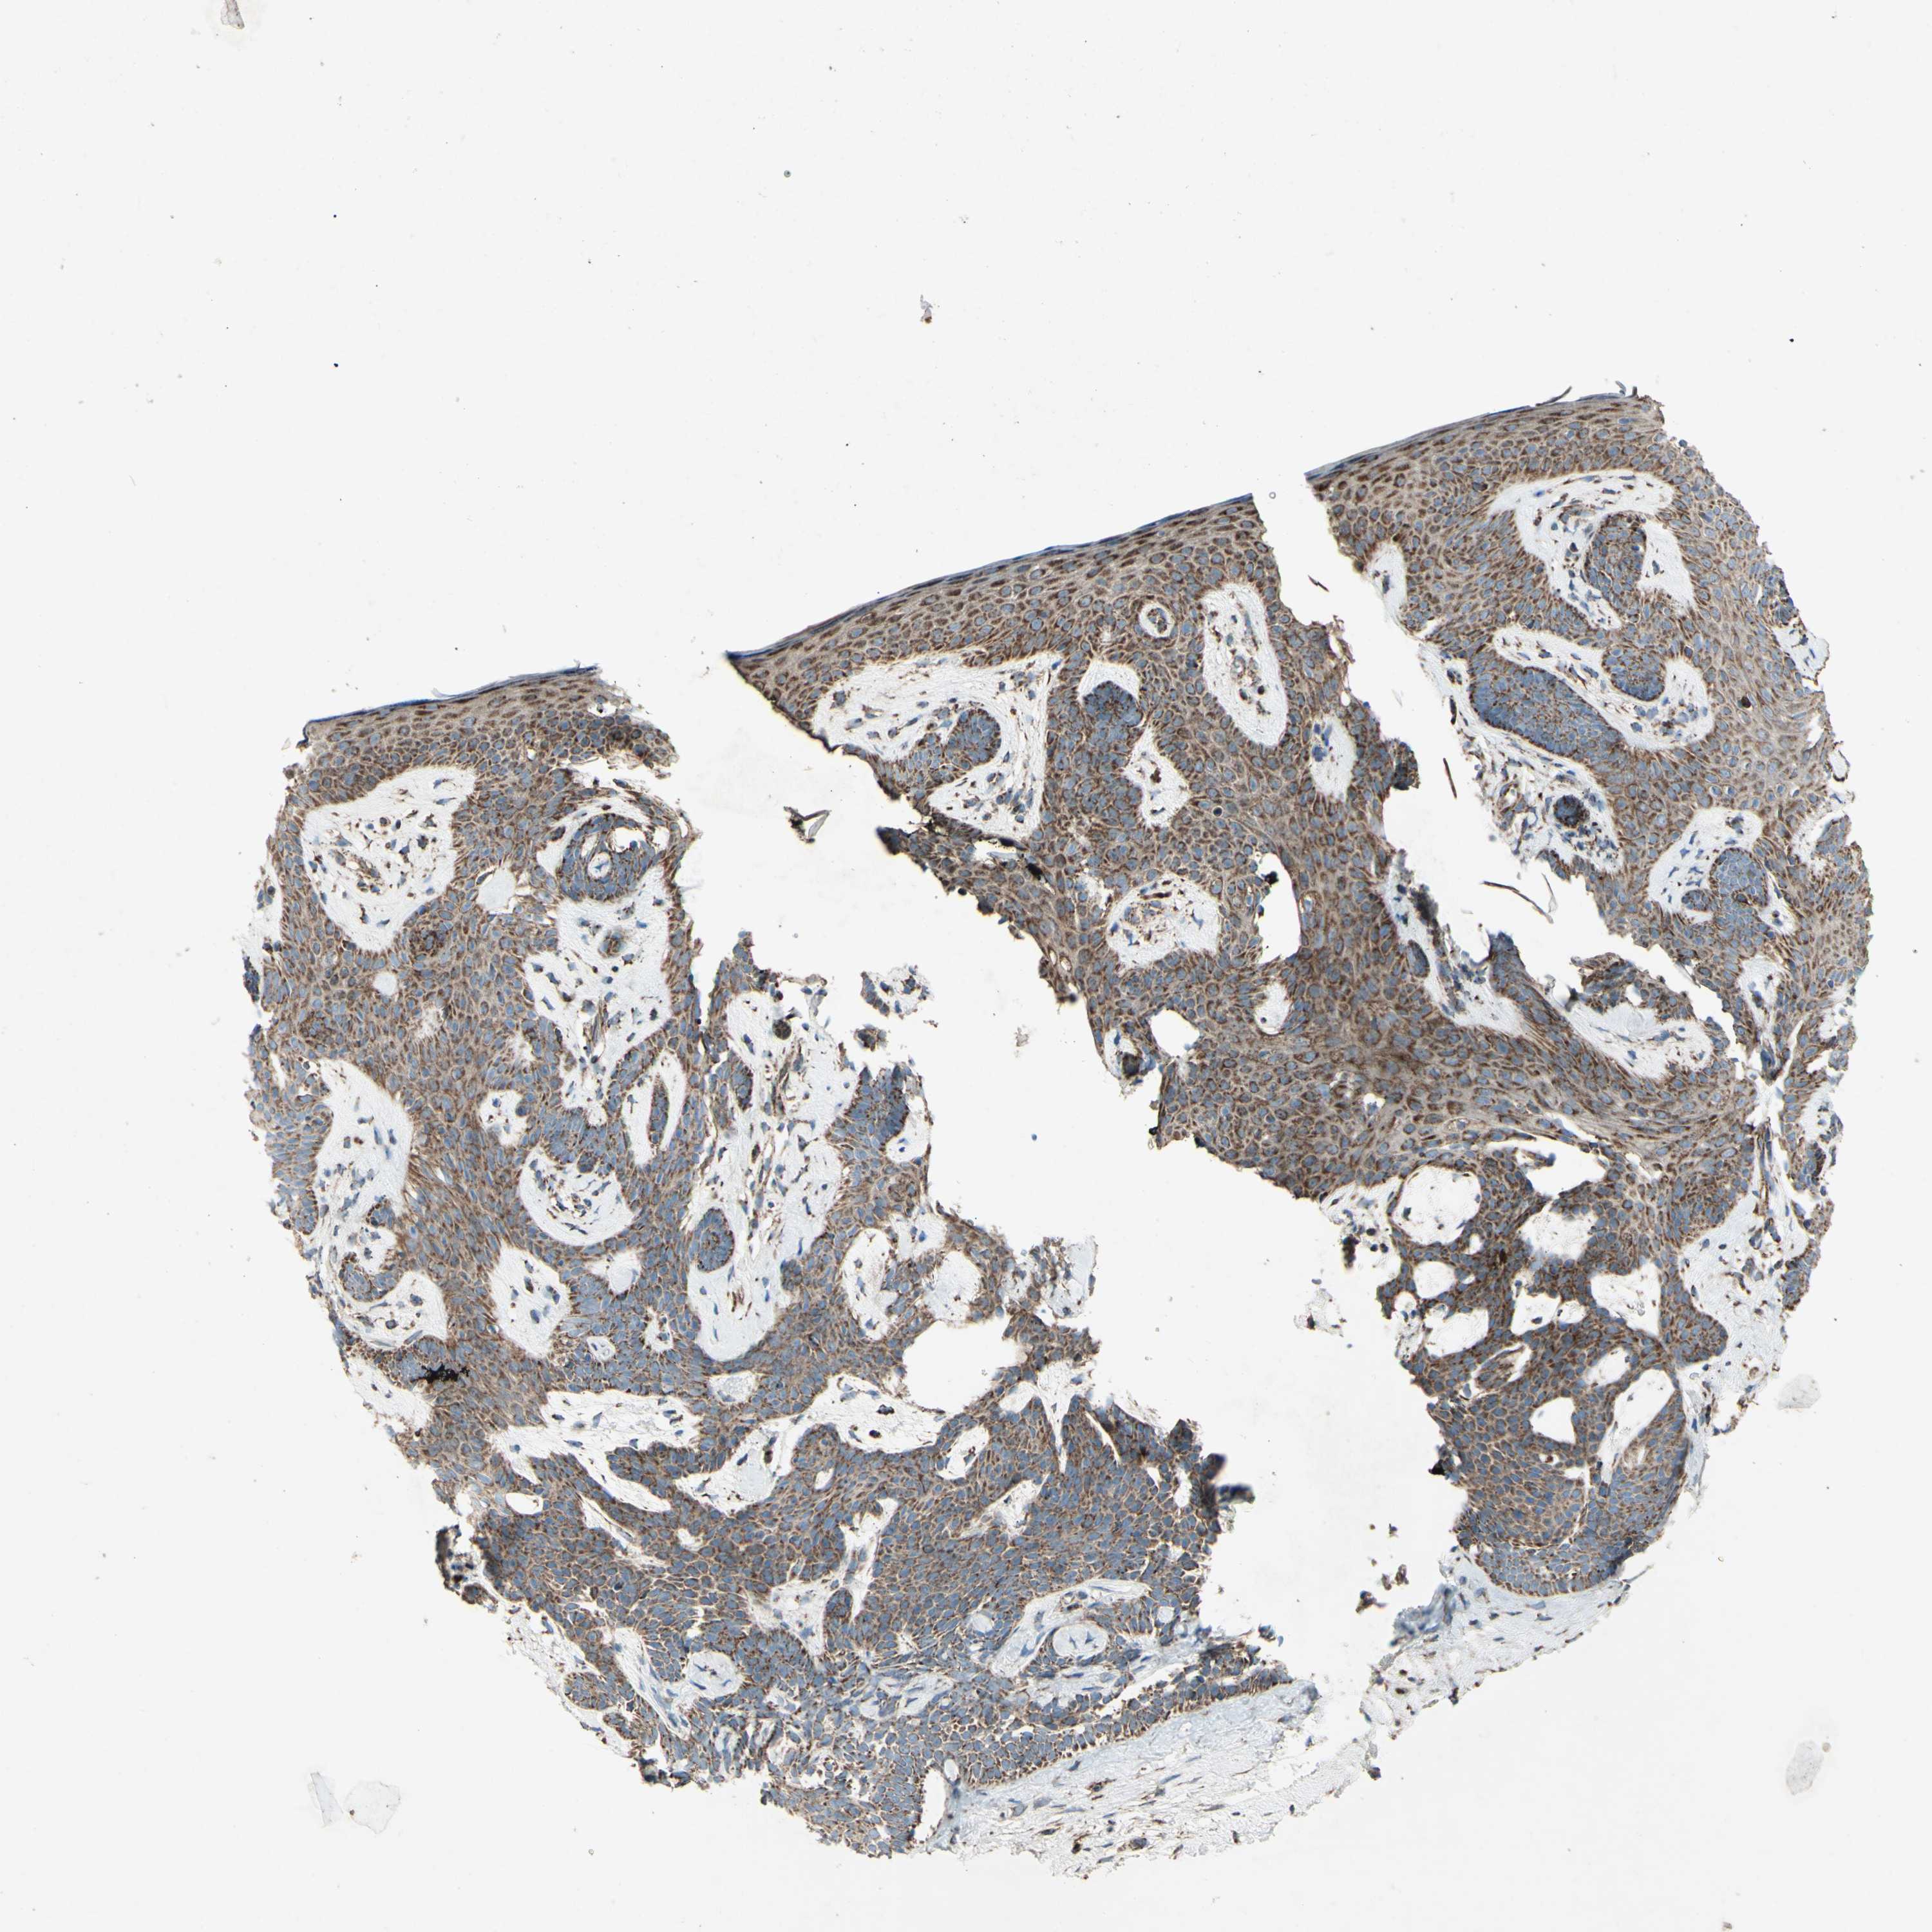

SKIN CANCER - Protein expressioni

A mouse-over function shows sample information and annotation data. Click on an image to view it in a full screen mode. Samples can be filtered based on level of antibody staining by selecting one or several of the following categories: high, medium, low and not detected. The assay and annotation is described here.

Each image is clickable and will lead to virtual microscopy that enables deeper exploration of all samples and also displays staining intensity scores, fraction scores and subcellular localization as well as patient and tissue information for each sample.

Antibody HPA010687

Staining

High

Medium

Low

Not detected

Intensity

Strong

Moderate

Weak

Negative

Quantity

>75%

75%-25%

<25%

None

Location

Nuclear

Cytoplasmic/membranous

Cytoplasmic/membranous,nuclear

Squamous cell carcinoma, NOS

Squamous cell carcinoma, metastatic, NOS

Basal cell carcinoma

Papilloma, NOS